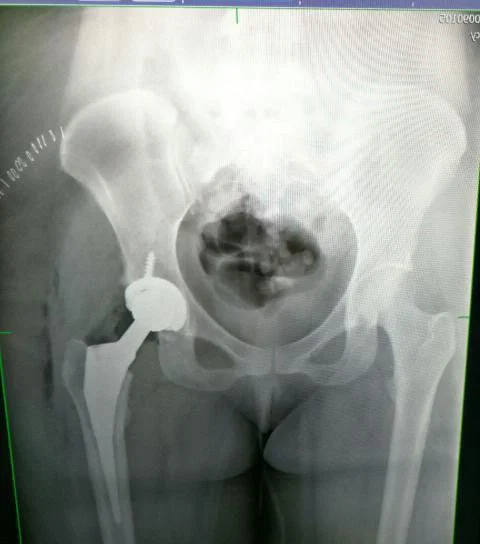

Después de ser operada de emergencia por una fractura en la cadera y una hemorragia cerebral, pasó seis semanas completamente en cama. Pero al terminar ese periodo, le dieron la noticia que más temía: la operación no había funcionado. Le tocó empezar de nuevo. Una segunda cirugía, esta vez con prótesis completa de cadera, la dejó otros seis meses sin poder caminar. También perdió parte de la movilidad en el pie izquierdo.